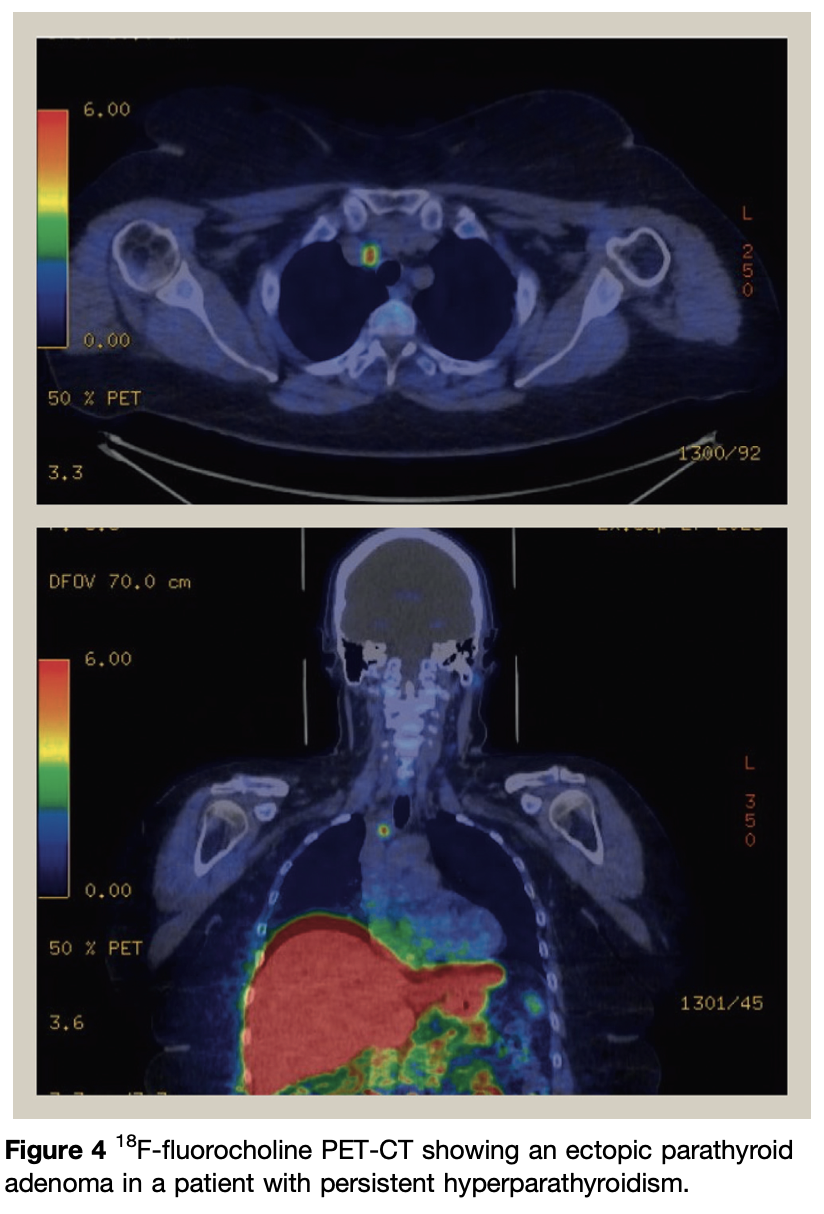

Several articles have reported the high sensitivity of 18F-fluorocholine PET-CT for the detection of parathyroid adenomas. Choline PET-CT can detect elusive parathyroids, including ectopic glands, and may be considered in the management of persistent or recurrent disease when other scans are negative

sensitivity near 100%